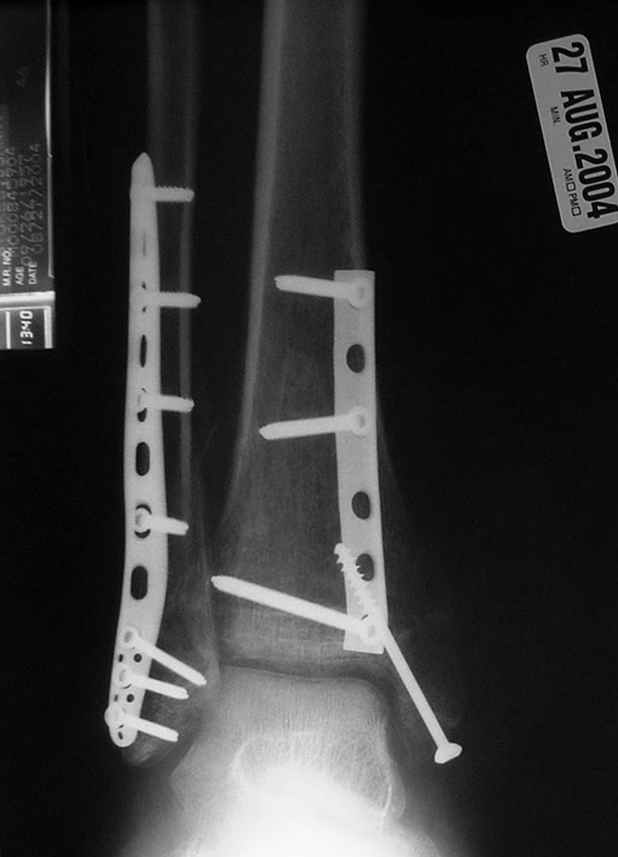

Re: ANKLE FRACTURE

Второй случай сделан из одного разреза

ЕЧ LISS plate, mininvasive approach - luxurous !

Вопрос практического характера - такой подход рутинный или при определенных показаниях и каких? Спрашиваю потому, что при потоке больных - закрытая голень, бедро, голеностоп и т.д. лучевая нагрузка должна быть немалая, каковы показатели дозиметра после такого операционного дня и при 2-3 операционных днях в неделю по 5-6 случаев (не считая ургентностей)?

На прямой проекции послеоперационного Рг макроскопически все выглядит очень анатомично, при микроскопическом ( :-)) ) рассмотрении можно все-таки заметить вальгизацию тарана, суставная щель в латеральном отделе сустава несколько уже , чем в медиальном при отсутствии латерального смещения тарана. У меня был аналогичный случай (без LISS , без мини доступа) с вальгусным наклоном тарана при восстановленном ankle mortise при последовательном наблюдении с интервалами в 6-8 недель в послеоперационном периоде отмечалось прогрессирующее сужение суставной щели в латеральном отделе сустава, закончившееся посттравматическим ОА, к счастью боли умеренные, купируемые аналгетиками или своими эндорфинами:-))(активная пациентка, у которой нет времени на болезни....) Какова жизненная ситуация в приведенном вами случае? И последнее, что я хотел бы прояснить для себя - фиксация внутренней лодыжки: я обычно комбинирую фиксацию компрессирующим винтом со спицей - по идее ротационная стабильность должна быть лучше, чем один винт, каковы ваши наблюдения в этом плане?